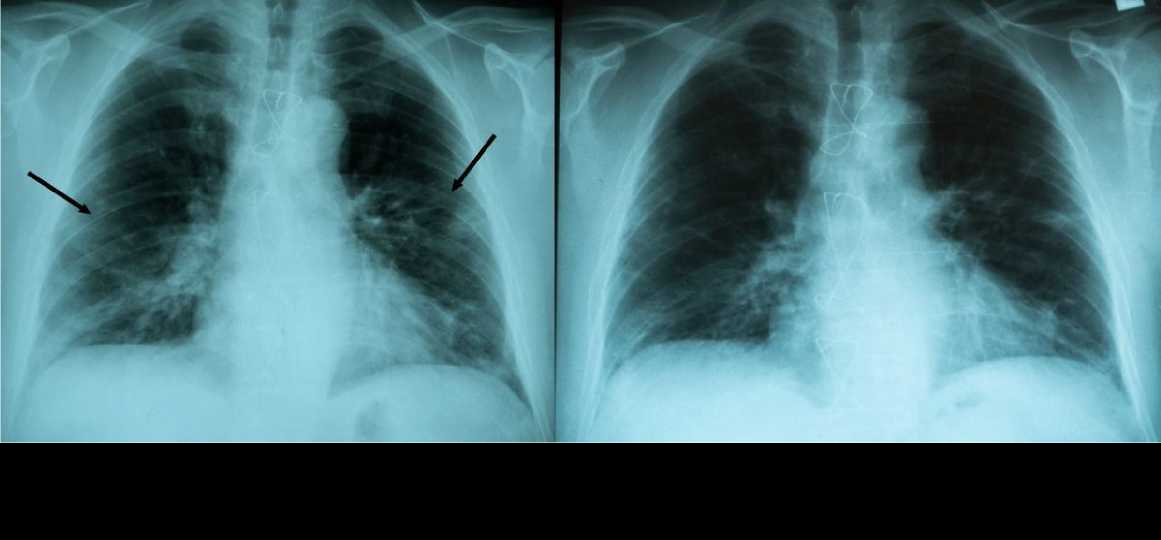

Results: The mean age of the patients was 55.9 years (SD=15), and most patients were male (60%). Despite the majority of patients 64% (n=35) suffering from comorbidities and 53% (n=29) of patients having been diagnosed with pneumonia, none of them died, and only four had required hospitalization in the course of COVID-19. Clinical stabilization was achieved in 91% (n=50) of patients within 48 hours after the first dose of amantadine with further improvement; additionally, all patients experienced remission of COVID-19. In total, 93% (n=51) of patients did not require hospitalization during the treatment.